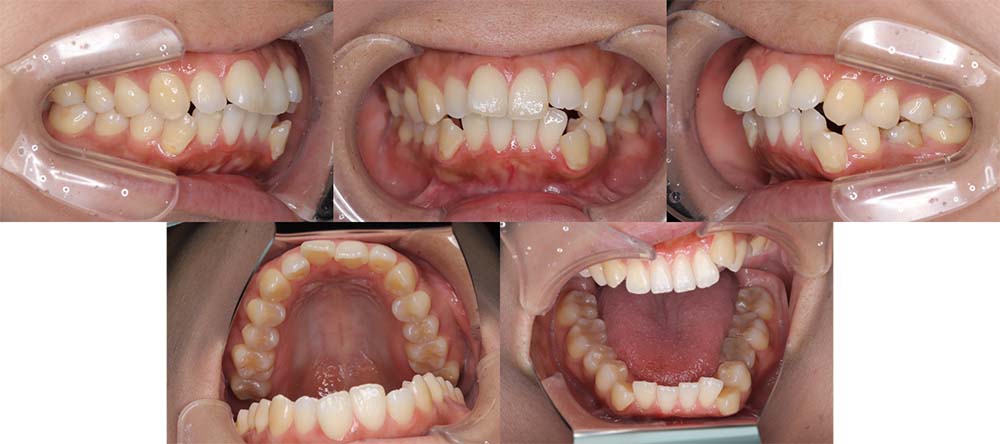

| 症例分類 | 上顎前突、叢生、シザースバイト |

| 診断名 | 右上7のシザーズバイトを伴う上下重度叢生skeletal2 |

| 主訴 | 歯並びが悪くて全体的にガタガタ |

| 年齢 | 19歳11ヶ月 |

| 性別 | 女性 |

| 抜歯部位 | 上顎左右と右下の第一小臼歯、左下の第二小臼歯(4本)、上顎右側第二大臼歯 |

| 使用装置 | 裏側のワイヤー装置 |

| 治療期間 | 2年11ヶ月(5ヶ月程度来院出来ない期間あり) |

| 保定装置 | 固定式保定装置、取り外し式保定装置(8時間) |

| 費用 |

[検査・診断料] ¥49,500 [基本施術料] ¥1,331,000 [調整料] ¥5,500/回 [抜歯] ¥5,500/本 [保定装置] ¥55,000(税込) 抜歯や虫歯治療は他院にて費用が別途かかります。(抜歯¥4,000〜10,000/本)

上下の重度叢生と上の歯が前方にあり上顎両側の第一小臼歯と下顎右側第一小臼歯、下顎左側第二小臼歯、上顎右側第二大臼歯(上顎右側親知らずを咬合に使用)を抜去して上下リンガルで治療を行いました。 左上の第二大臼歯部の咬合が深かったため、一時的に頬側に装置をつけさせて頂きました。裏側に装置を装着すると噛み合わせを浅くするためのバイトアップがかなりの量が必要になり咬みづらくなってしまうためです。

5ヶ月程度来院が出来なかった期間がありましたが、問題なく治療を終了することができました。